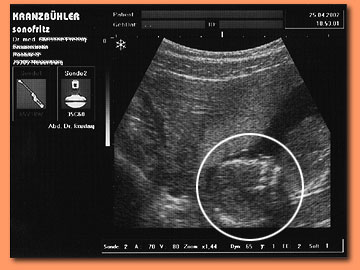

Das Zahnwachstum beginnt bereits im Mutterleib. Auf Sonografie-Bildern während der Schwangerschaft zur Überwachung der embryonalen Gesundheit sind bereits die entstehenden Zähne zu erkennen!

Zur Verdeutlichung haben wir in dem nebenstehenden Foto

den Kopf und die entstehenden Zähne eingekreist.